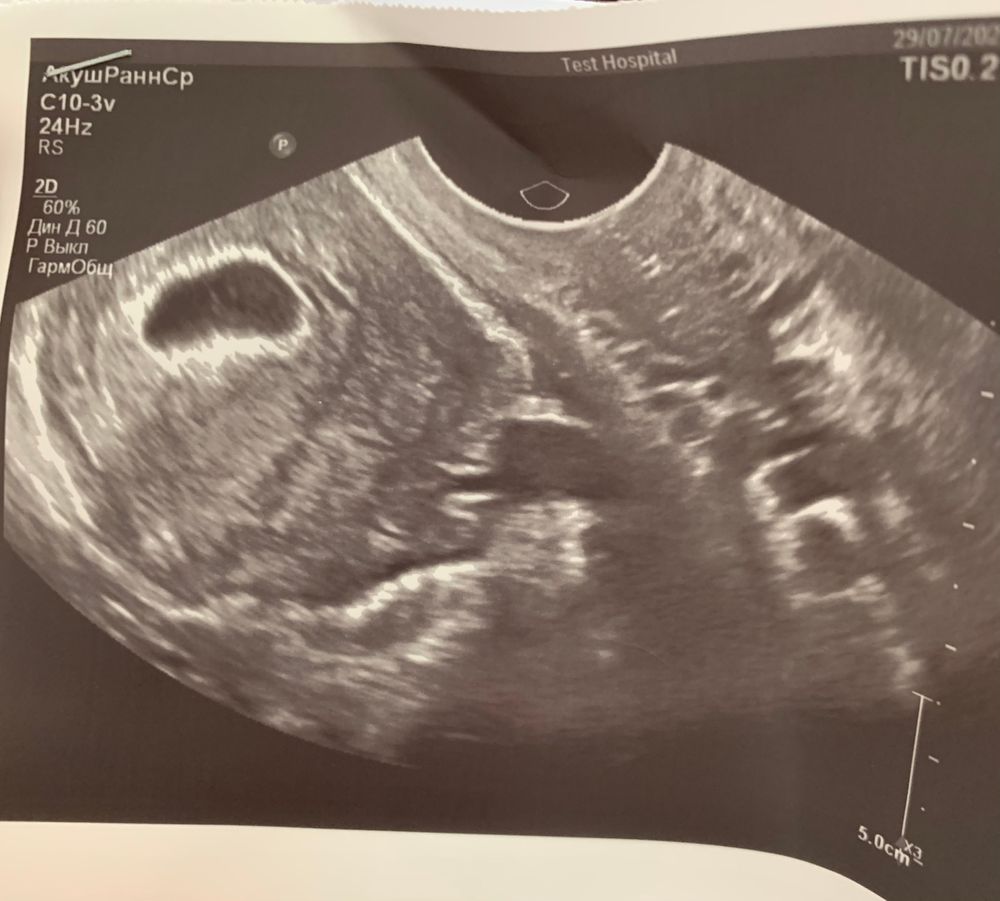

Изображение Всё видно. Идите через неделю к другому врачу.

Оля (я скоро мамой стану снова), я тоже не понимаю что за тени какие то, кучу узи всяких пересмотрела где пустое пя там полностью чёрное без всего, а тут вот, буду ждать может это и бусинка